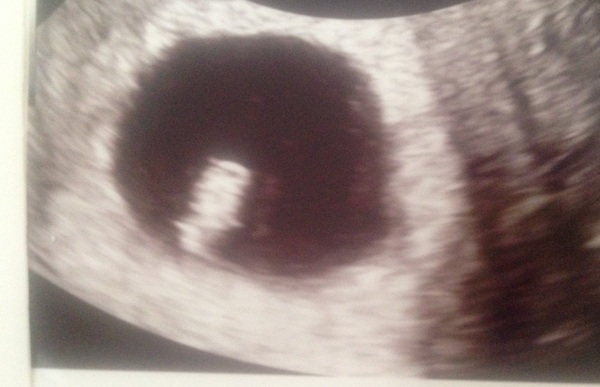

Saw a little heartbeat! X

Congratulations Ella Smile you must be so relieved - is that seven weeks? Feel free to upload the scan pic.

Yes ella! Let's see your little bubba!

Still feels like early days but very relieved that there was a little heart beating away this morning!

Ooh tiny little one Grin if you're anything like me Ella you feel better for about 45 minutes after each scan and then go back to worrying!

Hi little baby menopea SmileSmile

Yeah it's kind of a photo of my uterus but obviously it's already beautiful to me! Grin

You have a lovely uterus ella!